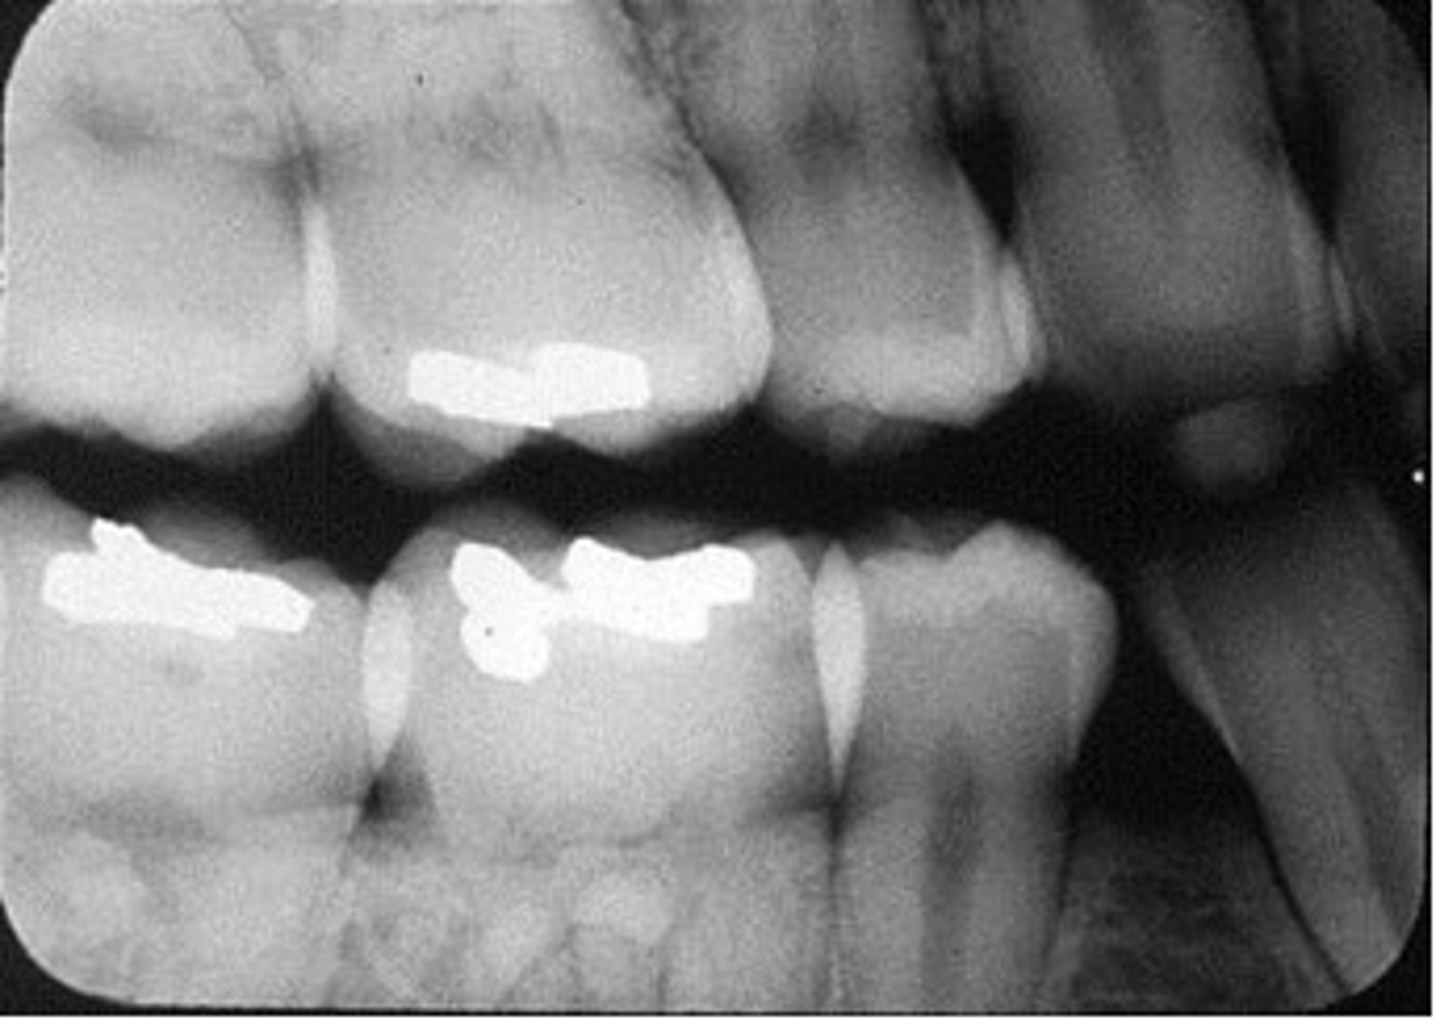

interproximal film

bitewing

shows crowns of both upper and lower teeth on same film

used to diagnose interproximal caries

sizes 0, 1, 2, or 3